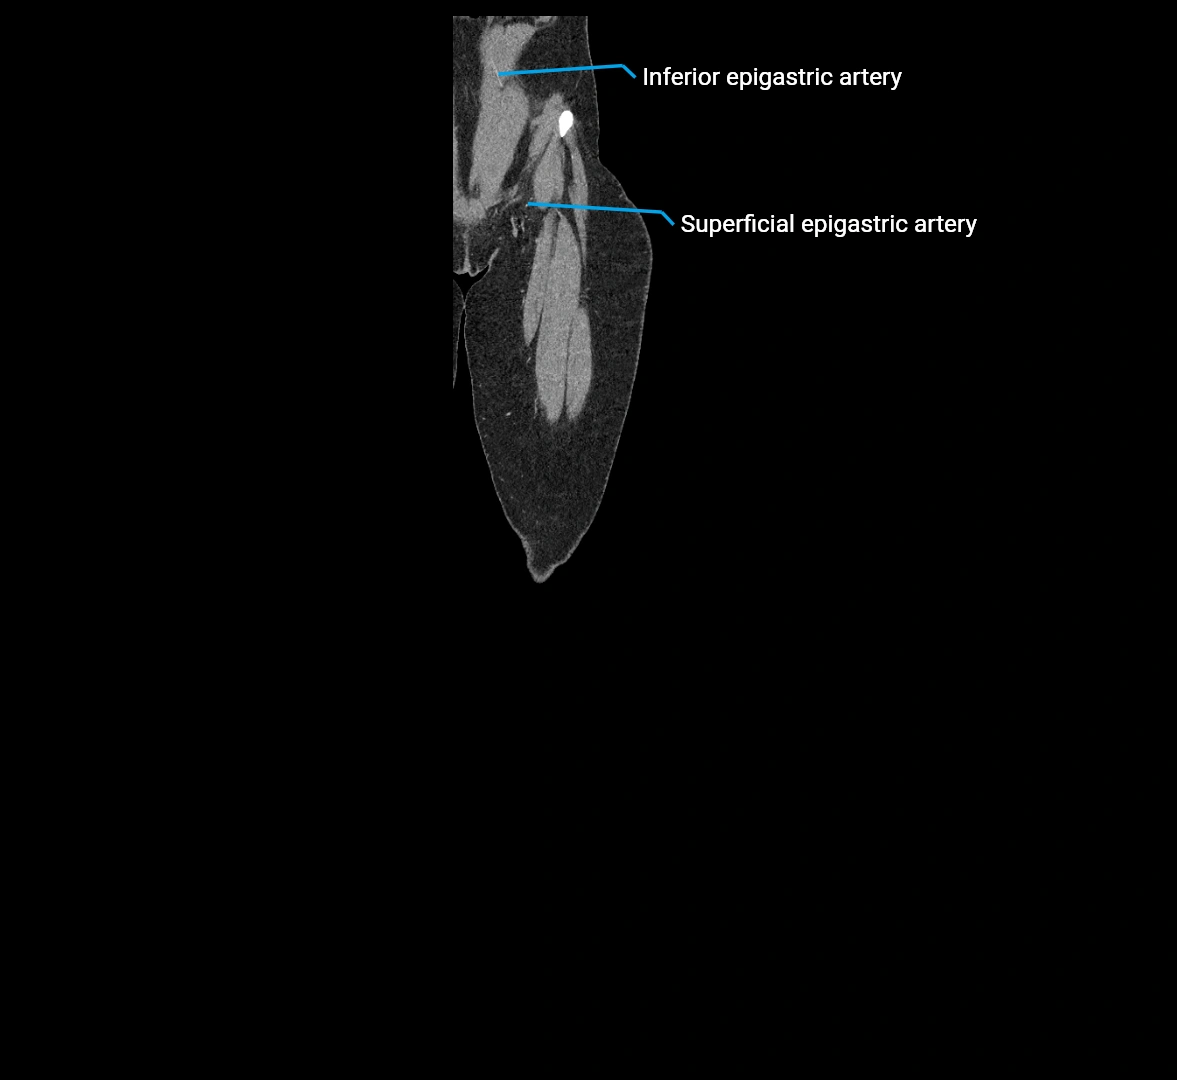

CT images

image